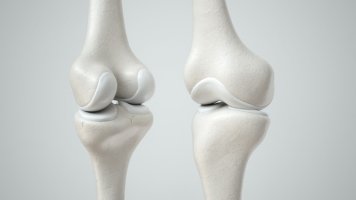

보통 사람의 연골은 60%~80%가 수분으로 구성되어 있고 그 밖에 콜라겐, 글루코사민, 콘드로이친, 히알루론산으로 이루어져 있습니다. 이 중 콘드로이친은 연골의 수분을 유지해 주고 뼈와 연골과 같은 조직을 형성하며 구성하는 성분입니다. 나이가 들어감에 따라 감소하는 콘드로이친은 20대부터 서서히 줄어들기 시작해 40대가 되면 20대의 절반으로 줄어들고 70대가 되면 75%가 줄어들면서 시간이 지나면 점점 더 없어진다고 합니다.

콘드로이틴은 연골에서 발견되는 가장 두드러진 물질입니다. 그것은 무릎의 골관절염 환자에게 도움이 될 수 있는 분해로부터 세포를 보호하고 유지함으로써 기능합니다. 여러 연구에 따르면 연골 손실률도 개선할 수 있습니다.